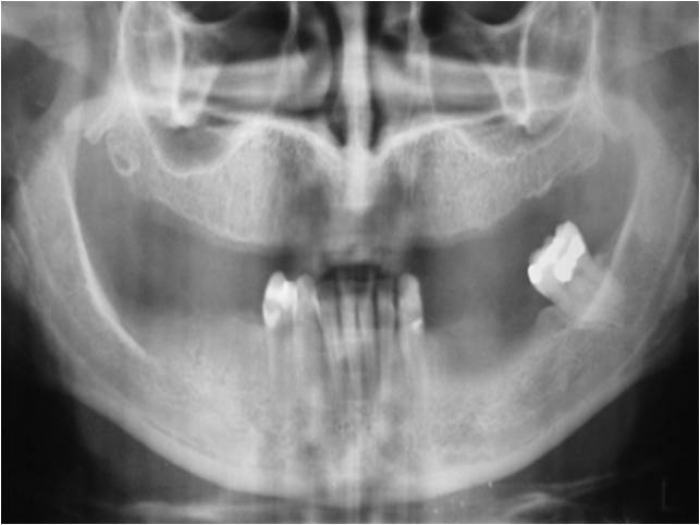

Raio X inicial